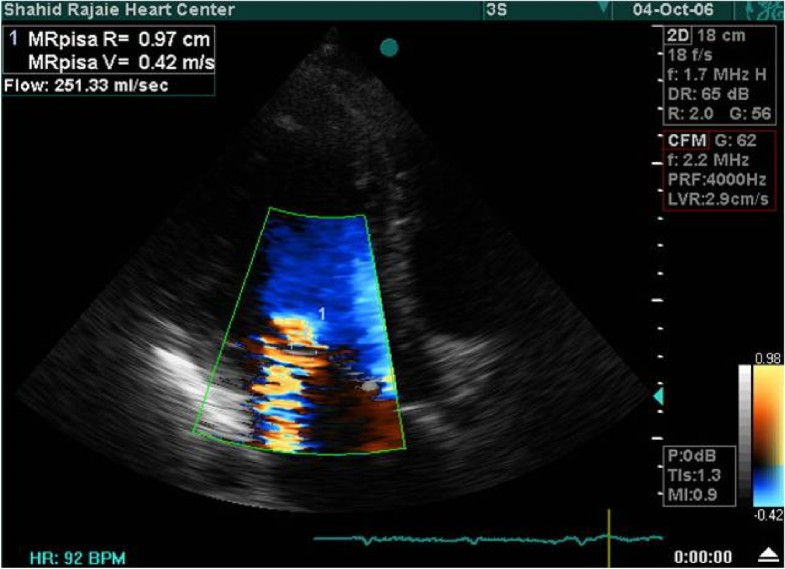

Echocardiographic Assessment Of Ischemic Mitral Regurgitation

Echocardiographic assessment of ischemic mitral regurgitation cardiovascularultrasound.biomedcentral.com

atrial mitral regurgitation distal quantification maximal echocardiographic ischemic vein pulmonary